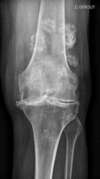

La radiologie confirme alors généralement l'importance de cette perte du cartilage articulaire (le cartilage n'est pas visible en radiologie), entraînant alors un rapprochement des structures osseuses entre elles (signe décrit comme un "pincement articulaire" sur les comptes rendus de radiologie). Des « becs de Perroquet » peuvent se former (ostéophytes) : ils témoignent d’une souffrance articulaire d’évolution lente.

gonarthrose genou gauche